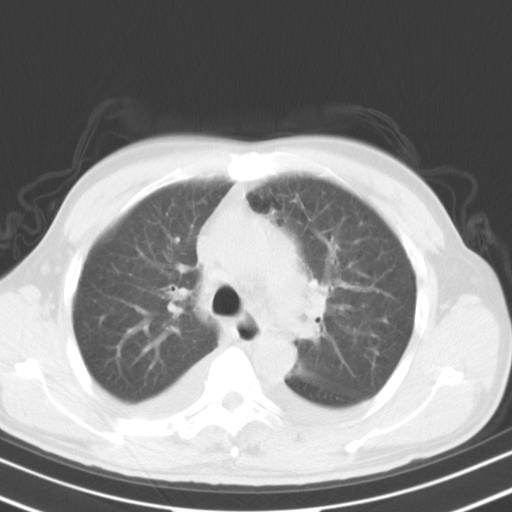

以下是引用zjzjr在2010-3-21 17:39:00的发言:[br]右下中心型肺癌并阻塞性肺炎/不张,纵膈淋巴结肿大,右侧大量胸腔积液,左侧少量胸腔积液

以下是引用zxl51642在2010-3-21 17:06:00的发言:[br]右下中心型肺癌并阻塞性肺炎/不张,纵膈淋巴结肿大,右侧大量胸腔积液,左侧少量胸腔积液,少量腹水。建议纤维支气管镜进一步检查。